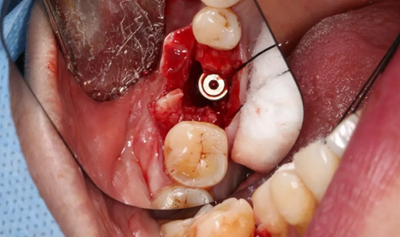

取下攜帶體,旋入封閉螺絲,潛入式愈合。

(攝于2017年4月14日)

組織瓣復(fù)位,常規(guī)間斷縫合。